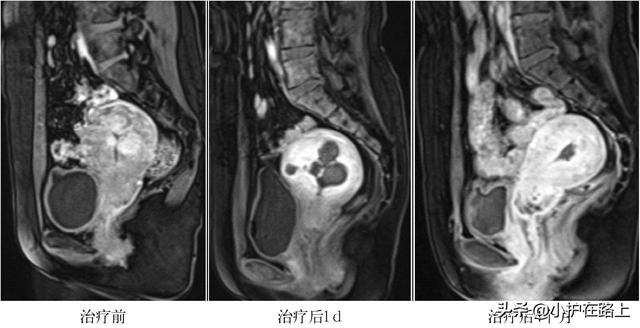

Uae 手术-微创介入治疗治疗机理 微创加介入疗法的原理:将曲张血管顶端结扎,再将药物注入曲张血管内,对病变血管内膜产生 无菌性炎症 反应,使病变血管粘连,以闭塞血管腔。 此疗法既避免了传统手术痛苦大、创伤大、费用高、风险大等诸多弊端,也避免了单纯UAE术后反应及注意事项 疼痛 疼痛与UAE 术后病灶及子宫的缺血相关,栓塞后缺血、坏死,大量炎性刺激因子释放导致疼痛。 术后疼痛为最常见不良反应,发生率几乎达到100%,疼痛程度因人而异,与个人疼痛耐受程度及栓塞程度有密切关系。 通常在结束手术时